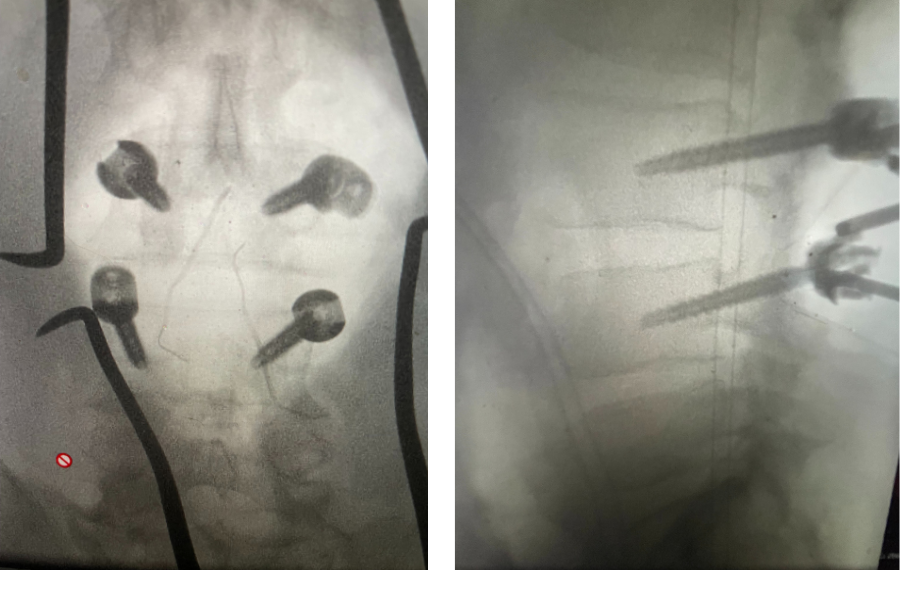

Figure 1. Sagittal T2-weighted MRI demonstrating severe L2-4 stenosis and slight grade 1 spondylolisthesis L3-4.

MRI demonstrated severe L3-4 stenosis with a grade 1 spondylolisthesis. He also had L2-3 stenosis. (Fig 1). On axial MRI (Fig 2) he had severe concentric stenosis at L3-4, but on careful examination it appeared that the right side had particular distortion of the anterior aspect of the thecal sac, perhaps secondary to a facet cyst. It seemed more likely coming off the facet joint and not a disc herniation. Although the right side was worse, most of his symptoms were on the left. Why does that happen? I don’t have a great explanation. Clearly the left side is also compressed but sometimes the body just chooses the side to be affected symptomatically when both sides are involved. This is true for compression of the spinal cord for instance in the cervical spine. What is not right, however, is that if a patient has a lateralized disc herniation and the opposite side is symptomatic and without compression, then one should not offer surgical treatment unless that disc is causing severe compression on one side with just less compression on the ipsilateral symptomatic side. Then one can argue that the pathology is having an effect on the opposite side if there is some degree of bilateral compression even if the ipsilateral symptomatic side is less compressed.